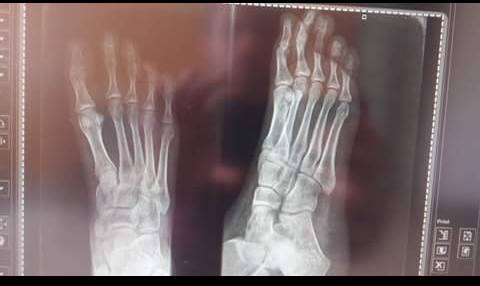

أغرب صورة أشعة فى مستشفى الطلبة فى الأسكندرية